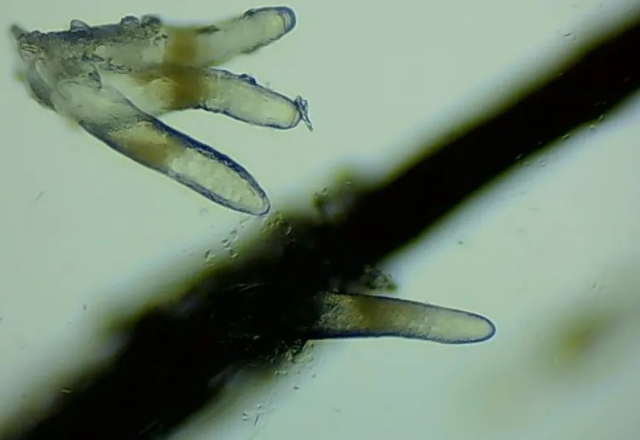

▲顯微鏡下,睫毛上的螨蟲,它們長著透明膠狀的身體,揮舞著爪子。

47歲的楊阿姨,近一個月來眼睛又干又癢,時不時流眼淚,一揉眼睛還有很多睫毛掉下來,為了查明病因,她趕忙來到廈門眼科中心就診。結(jié)果出人意料,顯微鏡下,楊阿姨睫毛上竟然寄居著不少“小蟲”,最多的有10多條?。?!